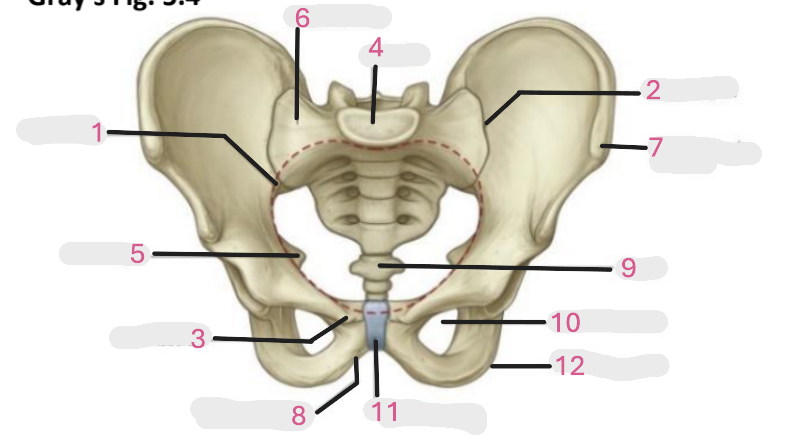

Where is the pelvic inlet

1

Where is the sacro-iliac joint

2

Where is the pubic tubercle

3

Where are the S1 body

4

Where is the ischial spine

5

Where is the ala of sacrum

6

Where is the anterior superior iliac spine

7

Where is the ischiopubic ramus

8

Where is the coccyx

9

Where is the obturator foramen

10

Where is the pubic symphysis

11

Where is the ischial tuberosity

12